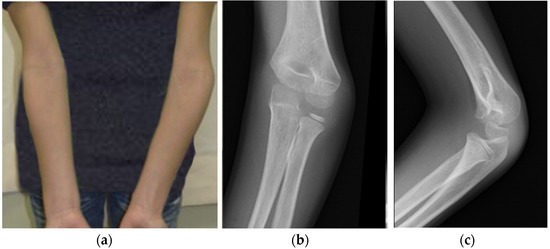

1.1. Cubitus Varus Syndrome

2.1. Study Design and Clinical Case